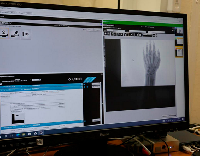

Мобильный рентгенаппарат + оцифровщик. Получение рентгеновского изображения на экране ноутбука. Вариант за 1,4 миллиона рублей под ключ.